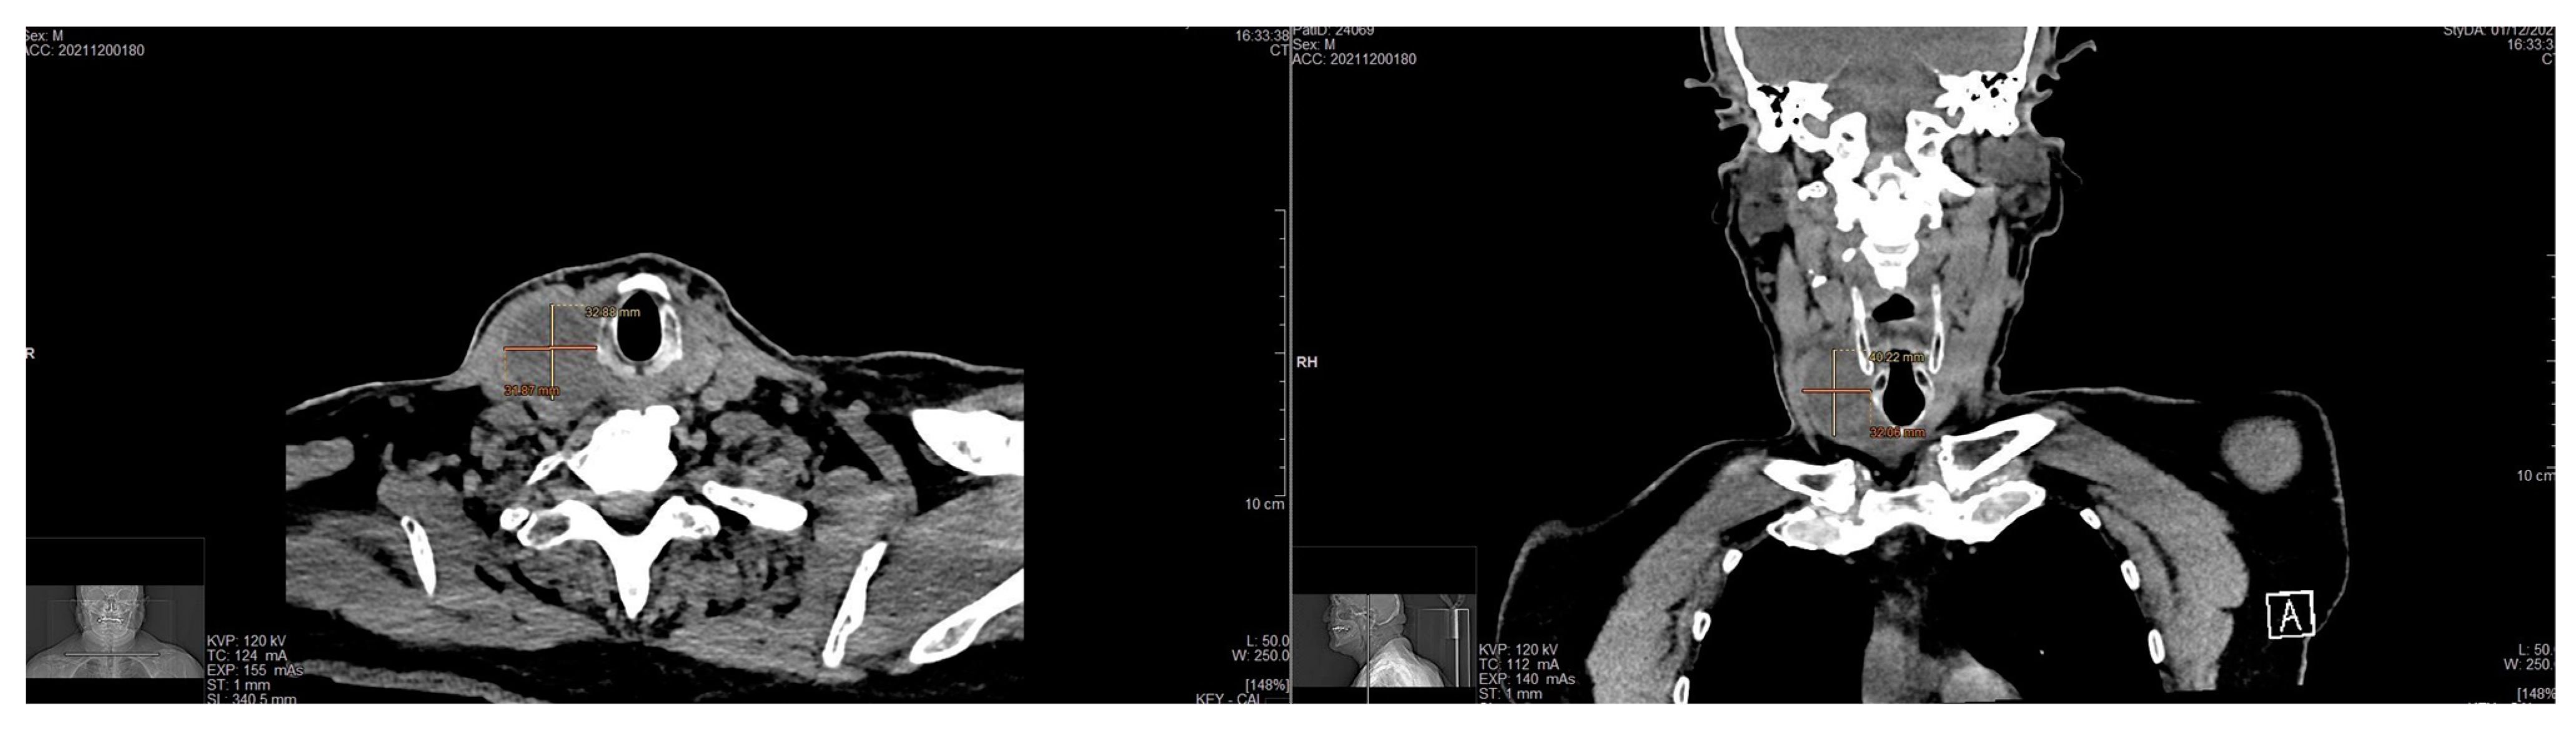

| Nagavalli et al., 2017 [28] | 60/F | Dysphagia, neck mass | Left thyroid lobe | US: Ovoid hypoechoic mass with smooth borders. CT: diffusely enlarged and heterogeneous thyroid with the left lobe extending to the retropharyngeal space and anterior mediastinum | Spindle cells with a lymphocytic background | Nodule Removal | Spindle cells in whorls with a predominantly Antoni A pattern | S-100+ Ki67 low proliferation |